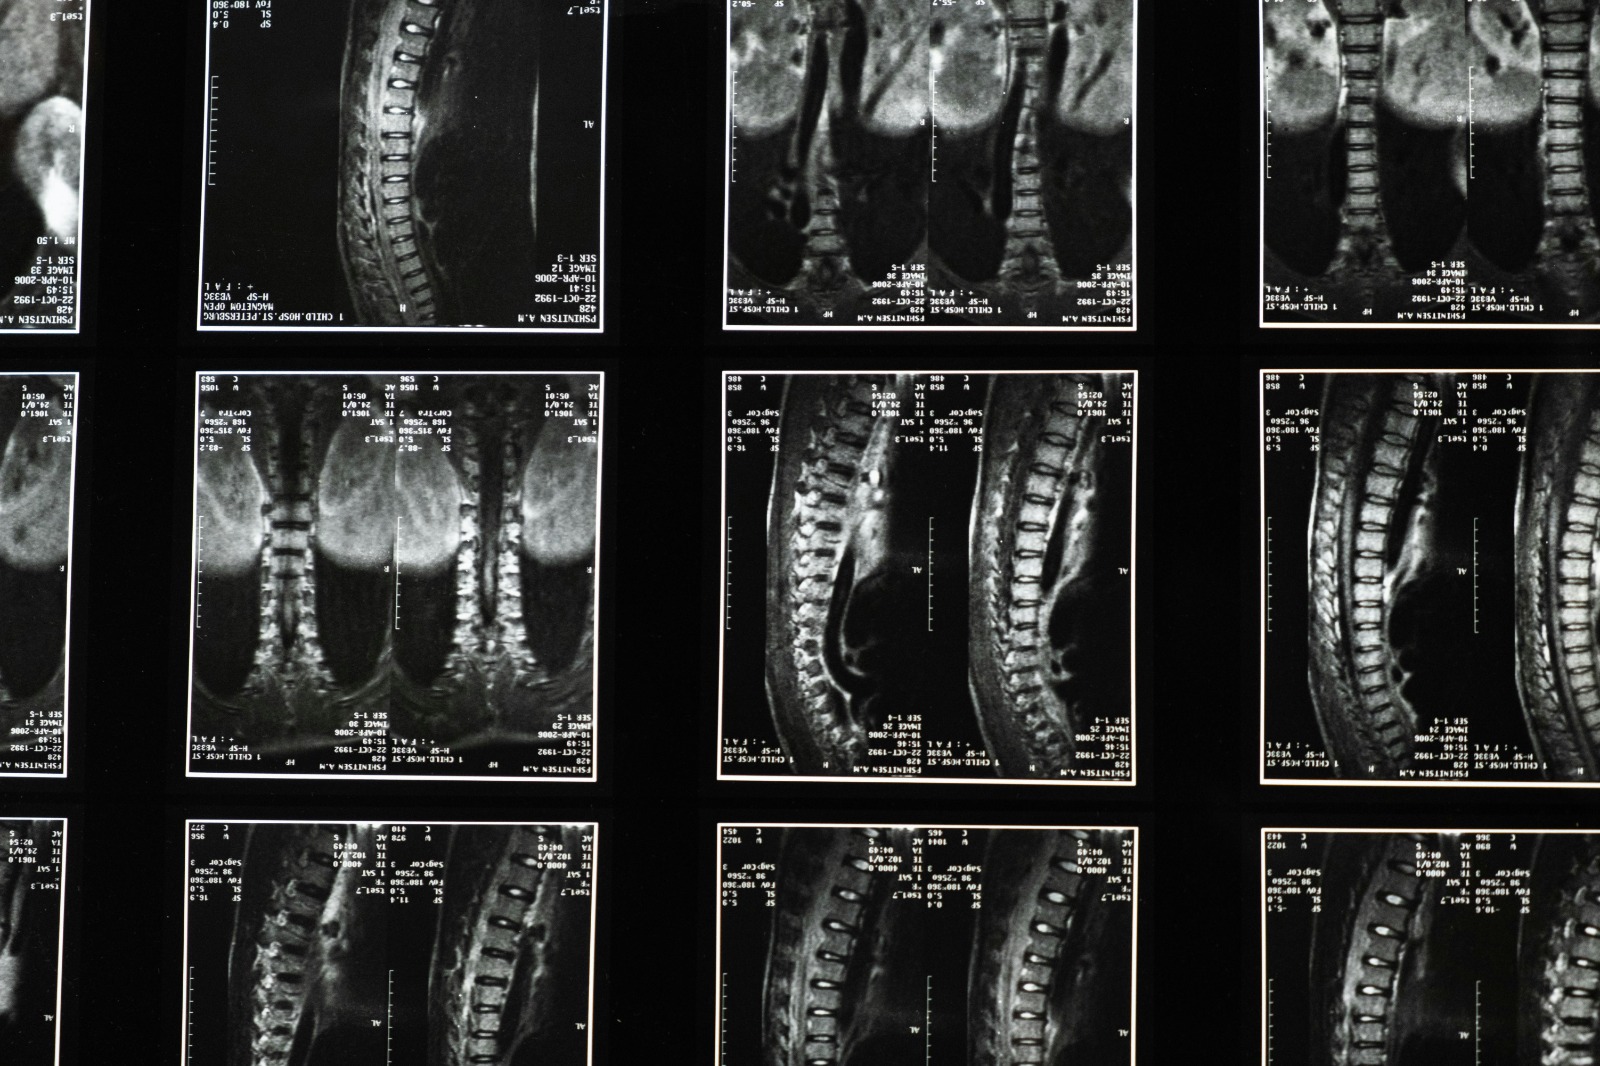

Sahabat Mikala, kanker tulang adalah kondisi ketika sel-sel abnormal tumbuh secara tidak terkendali di dalam jaringan tulang.

Penyakit ini bisa muncul langsung dari tulang (primer) atau menyebar dari organ lain (sekunder).

Beberapa jenis kanker tulang yang sering terjadi antara lain osteosarcoma, chondrosarcoma, dan Ewing sarcoma.